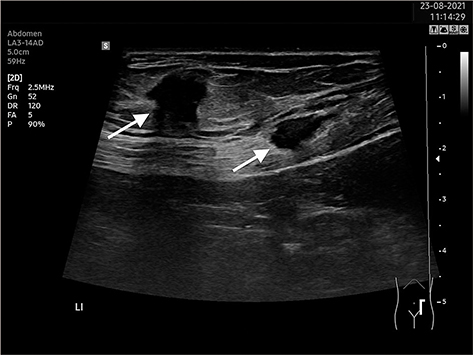

Een zeldzame oorzaak van littekenpijn na een sectio

Littekenpijn na een operatie kan hinderlijk zijn. Wanneer deze pijn hevig is of er een zwelling ontstaat, kan dit leiden tot hinder en ongerustheid bij de patiënt. Er zijn verschillende oorzaken voor littekenpijn, zoals een litteken-endometrioom. Dit is een zeldzame complicatie van gynaecologische operaties. We bespreken deze ongewone vorm van endometriose.